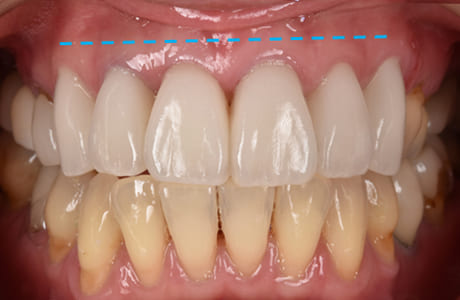

スマイル時の前後の比較

スマイル時の術前と術後の比較写真です。

術前は笑った際に歯ぐきの露出が目立っていましたが、術後は歯ぐきの見える範囲が大きく改善されているのがわかります。笑顔の印象もより自然でやわらかくなりました。